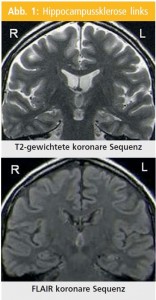

Zusammenfassend sind die typischen Eigenschaften der HS im MRT die Atrophie, Hyperintensität auf den T2-gewichteten Aufnahmen und Hypointensität auf den T1-gewichteten Aufnahmen sowie Verlust der inneren Struktur (Abb. 1).

MRT-Merkmale der Hippocampussklerose (HS)

Abnormale hippocampale T2-gewichtete Signale: Die verlässlichsten und sensitivsten Sequenzen für die HS-Diagnostik sind die T2-gewichteten FLAIR-Sequenzen (fluid-attenuated inversion recovery)14–19. Die hohen T2-gewichteten Signale entstehen auch:

Signal-Hypointensität des Hippocampus in den T1-gewichteten Sequenzen: Die Anwendung der T1-gewichteten Sequenzen, Inversion Recovery (IR), ist sehr hilfreich bei den Untersuchungen der HS, insbesondere wenn der Hippocampus unverändert auf anderen Sequenzen dargestellt wird15, 16. Der atrophierte Hippocampus zeigt ein reduziertes Signal in den T1-gewichteten Aufnahmen, was dem hohen Signal in den T2-gewichteten Aufnahmen entspricht. Die IR-Sequenzen ermöglichen die exzellente anatomische Unterscheidung der Strukturen, was typischerweise mittels T1-Sequenzen alleine nicht möglich ist.

Hippocampusatrophie: Die visuelle Begutachtung der optimal aufgenommenen und orientierten Schichten ermöglicht die verlässliche Diagnosestellung der HS mit einer Sensitivität von 80–85 %17, 19 und ist bei erfahrenen SpezialistInnen fast so gut wie eine Volumenmessung der Hippocampusgröße20.

Verlust der inneren Struktur des Hippocampus: Die normale interne morphologische Struktur des Hippocampus wird von Alveus, der molekularen Zellschicht des Gyrus dentatus und der pyramidalen Zellschicht des Ammonshorns gebildet. Das alles ist besonders gut an koronaren MR-Schichten darstellbar. Der Verlust der normalen inneren Struktur bei der HS ist durch den Verlust der neuronalen Zellen und Gliose verursacht. Die IR-Aufnahmen stellen nicht nur die anatomischen Details, sondern auch den Kontrast zu normalem Hippocampus dar. Die innere Struktur kann aber aufgrund des Alveus auf den weniger kontrastgefärbten Schichten (typisch für T1-Volumen-Sequenzen) im Vergleich zum klar abnormalen Hippocampus fälschlich als normal angenommen werden. Wichtig ist bei der Visualisierung der inneren Struktur des Hippocampus die Berücksichtigung der hohen räumlichen Auflösung und des Kontrasts18.